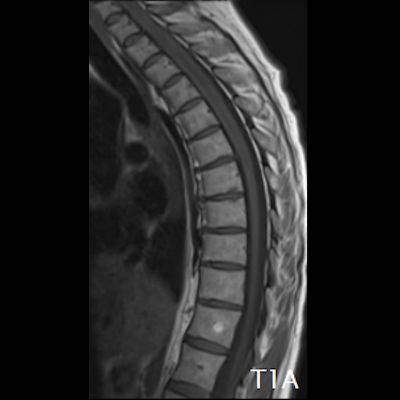

- (A) Torakal MRG’de sagital görüntülerde üst-orta torakal düzeyde T2A hiperintens (oklar), T1A izo-hipointens (ok) uzun segment ekspansil sinyal değişikliği izlenmekte olup sagital postkontrast T1A’da kontrast tutulumu mevcuttur (oklar). Bulgular longitudinal ekstensif transvers miyelit (LETM) ile uyumludur.

- Transvers miyelit sıklıkla santral gri cevheri etkileyen ve üç veya daha fazla vertebral gövde uzunluğunu etkilemektedir (LETM).

- Omurilik atrofisi ve ekspansiyon/ödem MS’e göre daha fazla görülür.